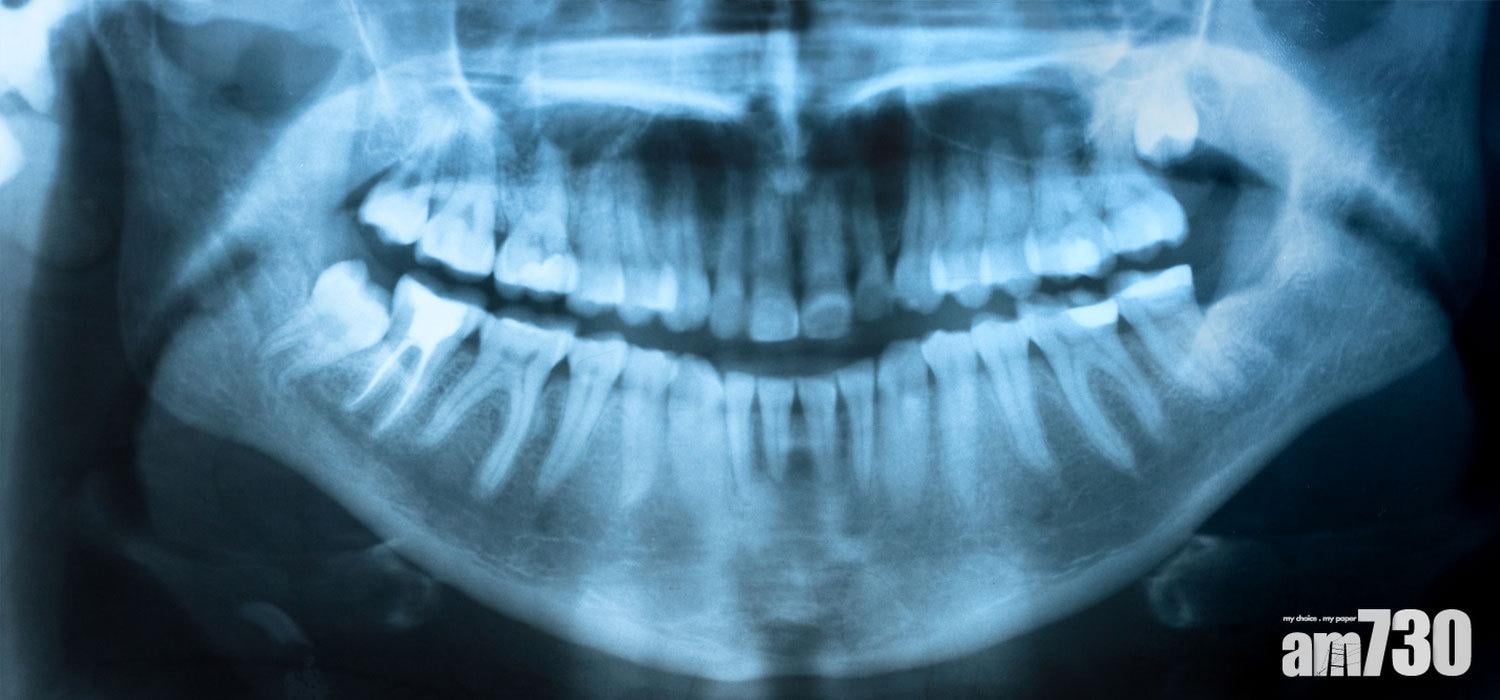

口外X光常用的是全景片(OPG),可同時顯示上下頜骨、牙齒和顳下頜關節的2D影像,較全面地顯示口腔狀況。3D錐形束電腦斷層掃描(CBCT)也屬於口外X光,相較於醫學用CT更普遍於牙科使用,其所產生輻射量遠低於醫學用CT。相比OPG,CBCT主要用於檢查牙骨與神經線,360度的拍攝使牙齒和骨組織的型態能被更準確的評估。